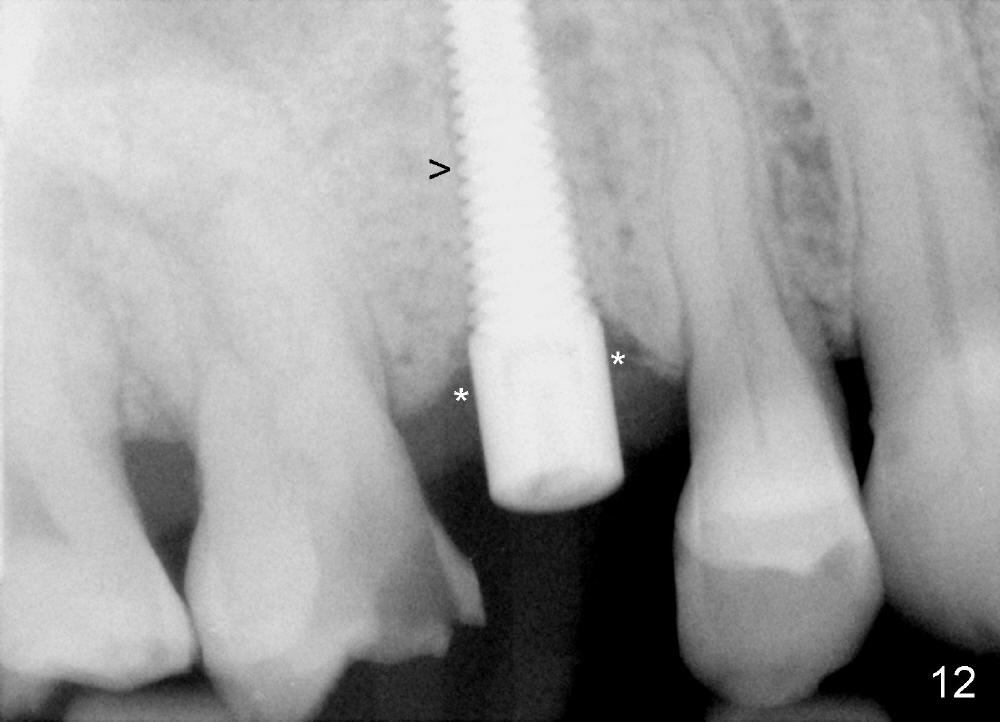

A 72-year-old man is a bruxer with #3 cusp fracture with chronic periapical radiolucency (Fig.1 *) and #4 acute crack.  It appears reasonable to take care of emergency (#4 extraction and immediate implant (Fig.3-7: 4.5x20 mm, 45 Ncm)) followed by root canal therapy or extraction for #3.  Eight (Fig.8) and 14 (Fig.9-11) days postop, the patient is doing fine and the wound heals normally.  But he does not agree any treatment for #3, since it is asymptomatic in spite of a fistula associated with the tooth (Fig.8,9 >).  Three months postop, the patient is still asymptomatic and is ready for #4 restoration since the tooth #28 cracks.  Follow-up PA shows the persistent distal gap (Fig.12 >, as compared to Fig.4), accompanied with crestal bone resorption (*).  Clinically the implant has mild mobility and light tenderness. The patient still refuses #3 treatment. It appears that the implant has failed to osteointegrate.  In brief, do not place an immediate implant next to active infection.

Five and a half months postop, the distal gap appears to have reduced (Fig.13 >).  Clinically the implant is stable and is ready for restoration.  It is advisor able to watch those asymptomatic immediate implants with minimal mobility.  It takes time to osteointegrate the immediate implant considering the peri-implant space.